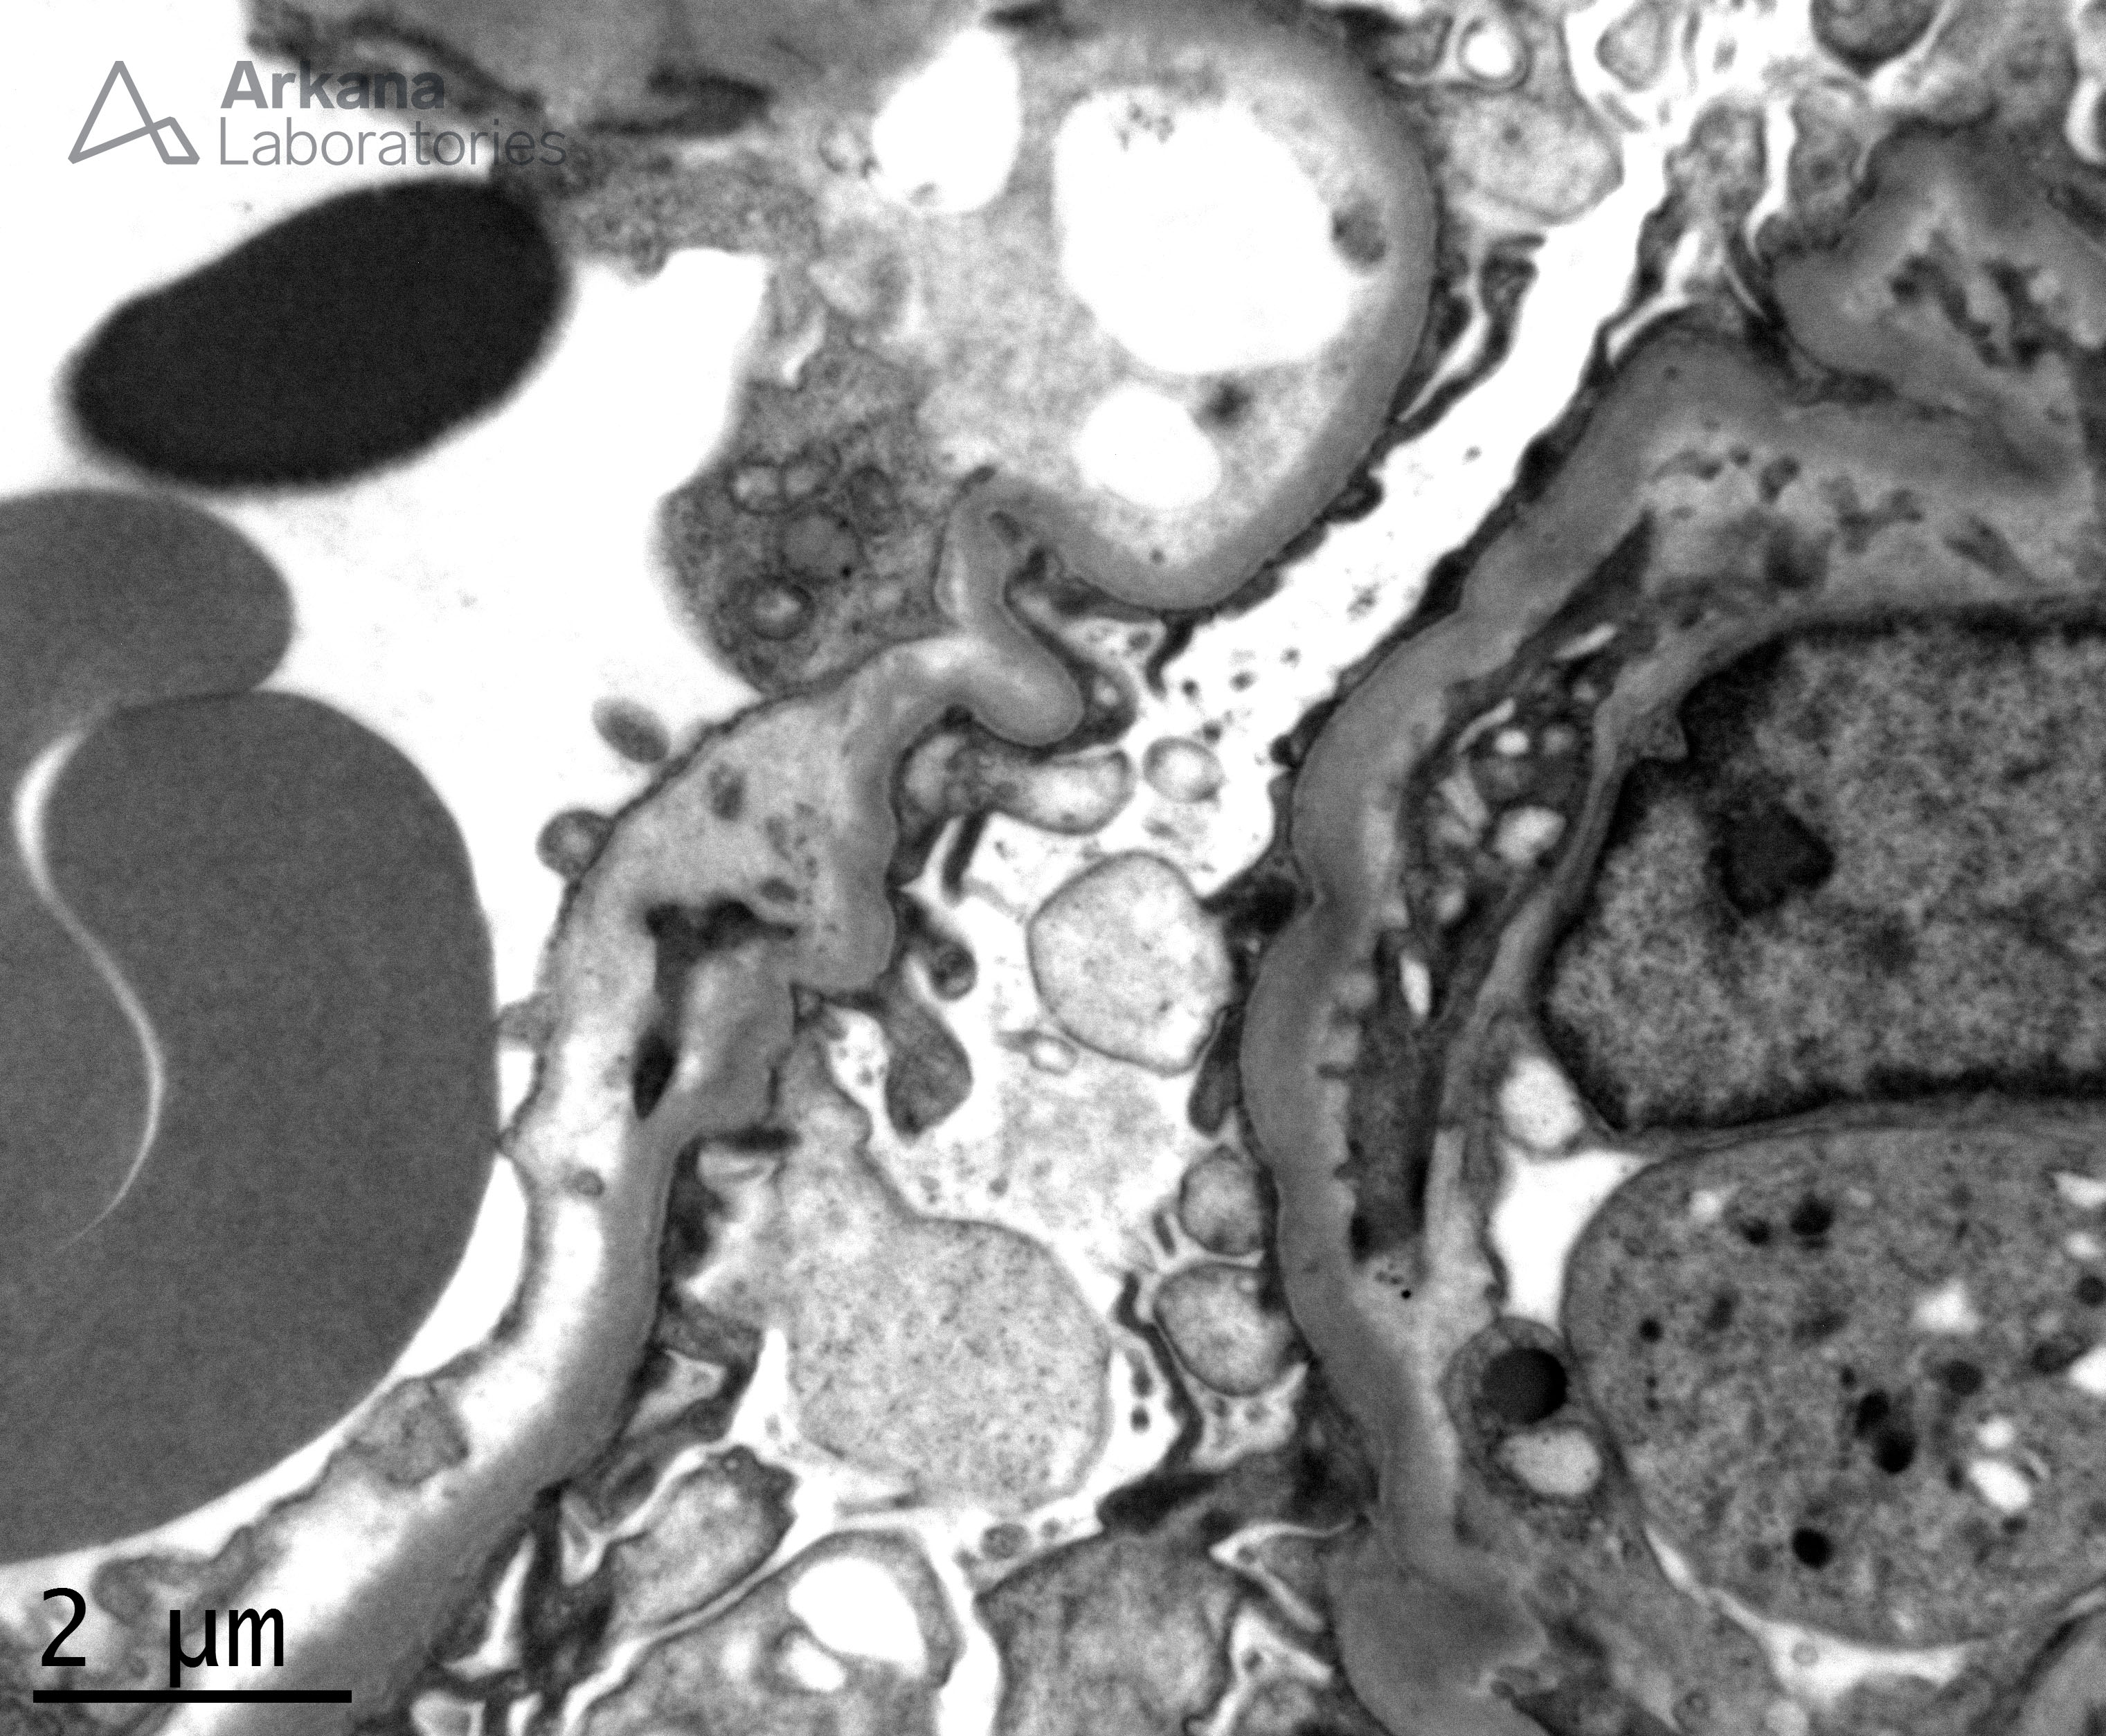

GBM with Subendothelial Electron Lucent Widening_2